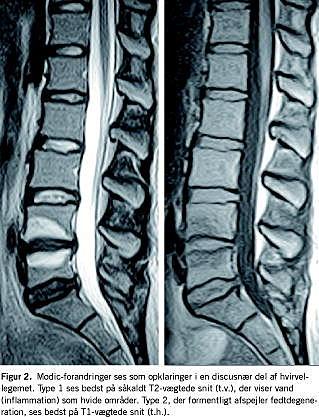

Modic-forandringer

Discusdegeneration har man langt overvejende opfattet som radiære sprækker i discus. En ny erkendelse er, at udsiven af nucleusvæv kranialt/kaudalt gennem dækpladen til hvirvel-legemernes tilstødende dele kan fremkalde inflammatoriske knogleforandringer (Figur 2 ). Først præges billedet af lokalt ødem (type 1), senere af fedtdegeneration (type 2). Sådanne forandringer fundet ved MR-skanning korrelerer bedre til længerevarende, intermitterende rygsmerte, end f.eks. discusdegeneration gør [4]. I et materiale med konsekutive patienter med > 4 mdr. varende betydende rygsmerter var der forandringer hos 40%. En del tilfælde opstår i efterforløbet af en prolaps. Der arbejdes (forår 2006) med en teori om, at nogle tilfælde kan skyldes ellers apatogene bakterier, der slipper ind i nucleus gennem åbningen, som prolapsen har fremkaldt [5]. Klinisk set er billedet ikke specielt anderledes end ved anden længerevarende rygsmerte, men tilstanden synes at respondere dårligere på træning.